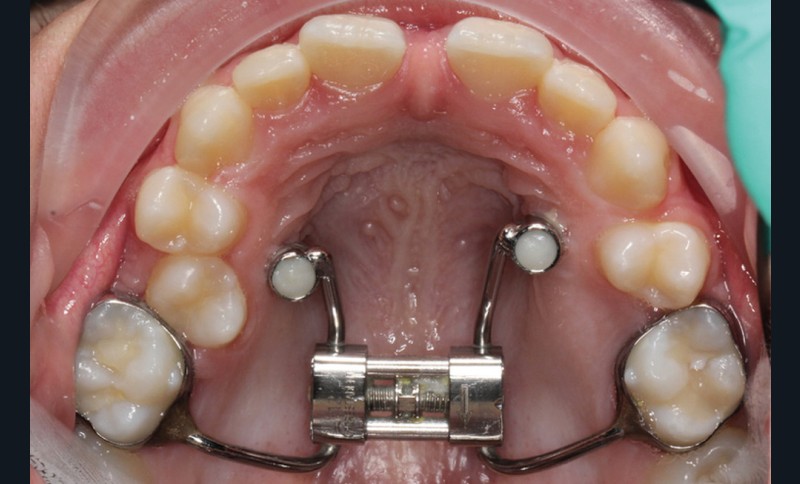

C’est à ces questions que nous permettront de répondre les deux premiers conférenciers, parodontologistes : le Dr Béatrice Straub nous présentera le renfort parodontal minéralisé, technique qu’elle a développée et pratique depuis de nombreuses années, pour éviter les préjudices des mouvements orthodontiques à risque, notamment lors des décompensations préchirurgicales (fig. 1a-d) ; le Pr Anton Sculean abordera le thème des greffes, avec leurs indications, les différentes techniques à privilégier et illustrera ses propos par de nombreux cas cliniques aux résultats esthétiques impressionnants.

À côté de la coopération moindre qu’ils exigent, les ancrages squelettiques présentent également l’avantage de répondre à des indications très variées : correction des sourires gingivaux (Dr Skander Ellouze, fig. 3a-c), distalisation ou mésialisation molaire, supports pour les masques faciaux, mini transpalatin sur vis après expansion, ressorts de rétraction pour mettre en place les canines incluses sans léser les racines des dents adjacentes [3] (Dr Stéphane Renger, fig. 4) ou appareils d’expansion maxillaire (Dr Hans Winsauer, Dr Guido Sampersmans, fig. 5a-c)…